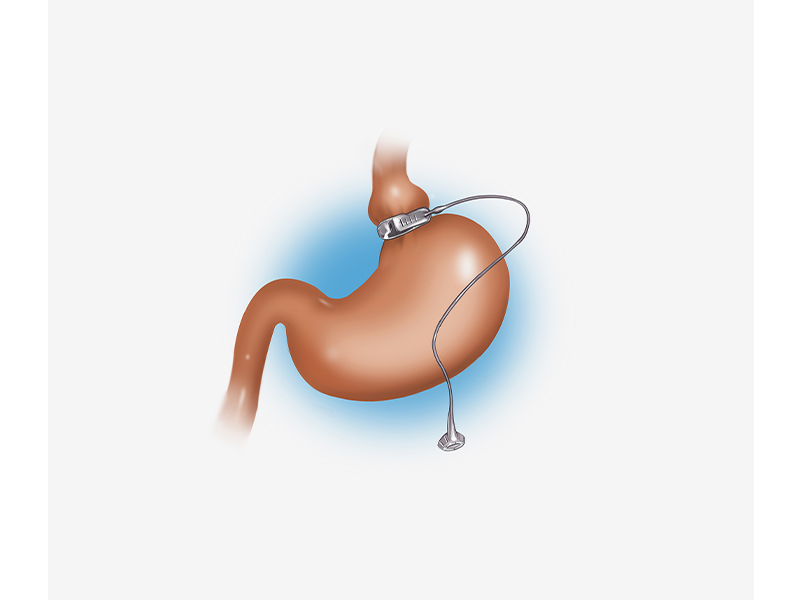

قیمت: 45٬000 تومان - دسته بندی فایل: پاورپوینتپاورپوینت آشنایی با عمل باندینگ معده

خرید پاورپوینت حرفه ای با موضوع آشنایی با عمل باندینگ معده از لوکس فایل